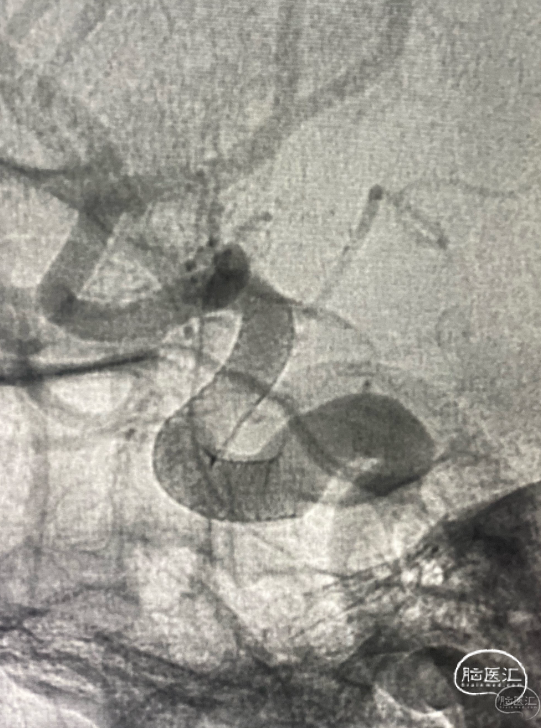

第一台手术结束。开始第二台,一个复发大脑中动脉瘤,复发部位虽然不大,但毕竟是出血动脉瘤,还是远期继续增大再出血的风险。

Lvis jr小支架辅助小弹簧圈栓塞,很好的解决的复发部分。

再次造影,没有动脉瘤的显影了,远期再复发的几率就很小了。